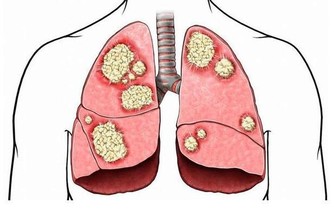

胃病很常見,主要臨床表現為胃痛,大多由於人們的情緒因素、飲食不健康、作息不規律,沒有註意保養胃,導致越來越多的人患上了胃病,今天我們聊聊胃痛吃什麼食物好。

胃痛又稱胃脘痛。如果將腹部劃分為四個區域來看,左側偏中上的部分這一區域的疼痛,最有可能是胃痛。廣義來講,平肚臍以上至肋弓劍突下都屬於胃的區域。

導致胃痛的原因有很多,如胃酸、膽汁返流引起的、患有胃潰瘍、十二指腸潰瘍潰瘍、胃痙攣等,大多與進食有很密切的關係。